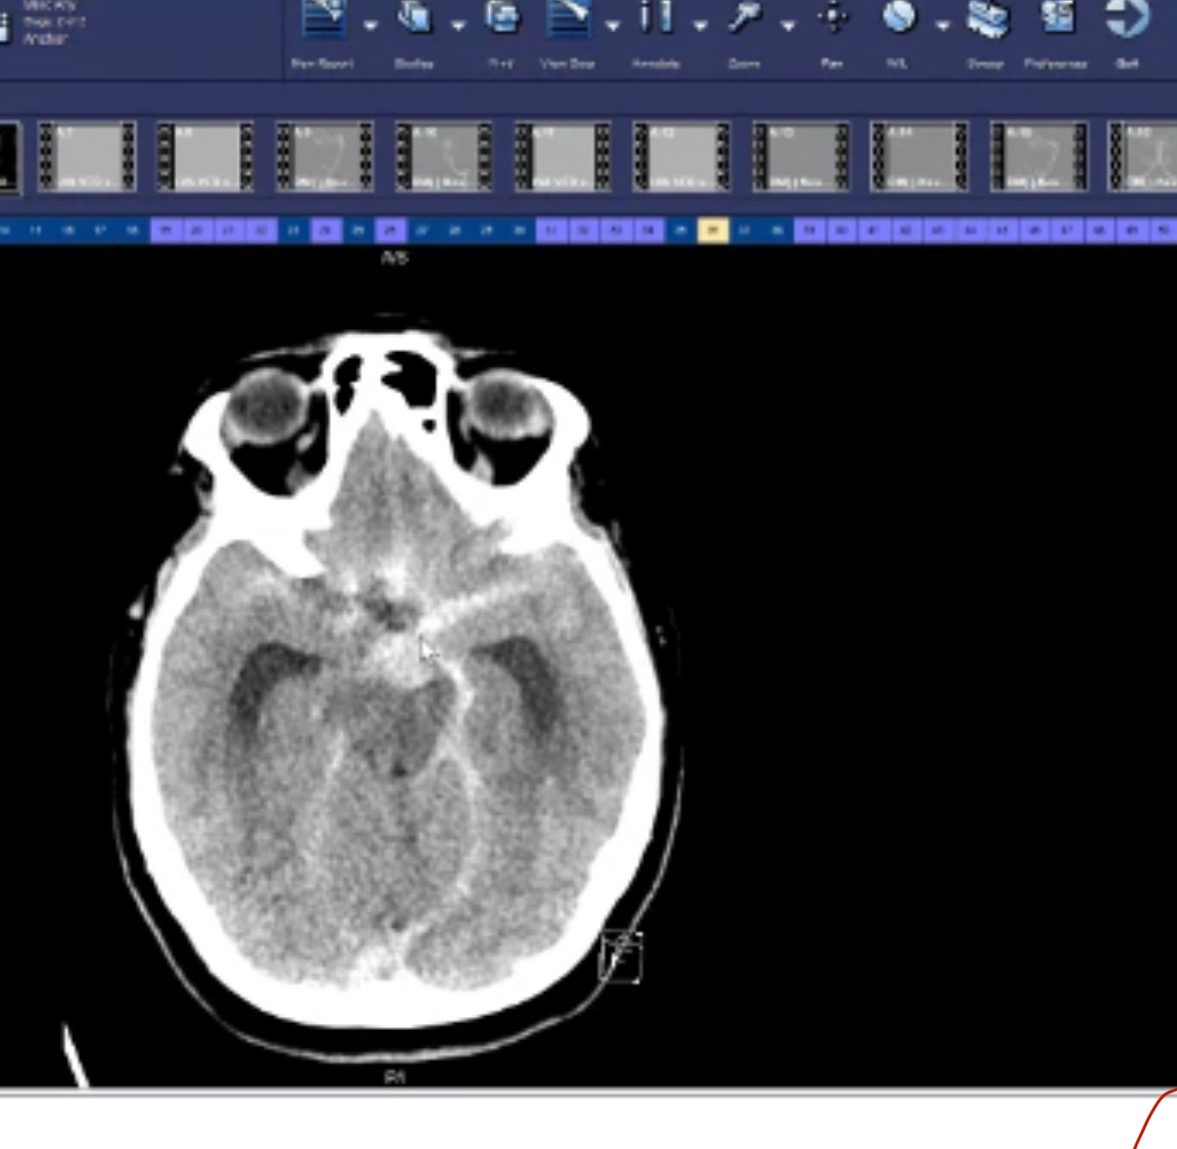

In April 2025 Laura suffered a ruptured brain aneurysm, my sister & I found her unconscious at home. She was rushed to St Vincent hospital in Indianapolis, IN. There we were told about the aneurysm rupture, that required emergency coiling surgery to stop the bleeding. She was in Indy for over 2 months , in that time she underwent two surgeries to secure the brain aneurysm , suffered two strokes and ended up on ventilator and trach , which she was eventually weaned from!